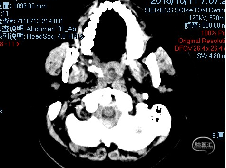

辅助检查

9小时前工地施工时不慎从高约两米的地方落下,落地时被手中所持钢钎自右颌下向左上穿入口腔及颅内,经口腔咽喉部至左额顶部穿出,伴出血、剧痛,无昏迷,无四肢活动障碍,无脑组织漏出,急诊入当地医院,头部CT示:颅脑贯通伤。当地医院及消防队员试行取出异物未成功,患者口鼻出血多,当地医院紧急行“气管切开术”并给予补液等对症治疗,约4小时后患者伤处疼痛加重并伴有呕吐,为进一步诊治急送我院。

术后CT

左侧颈内动脉虹吸部受压变扁,余未见明显异常。